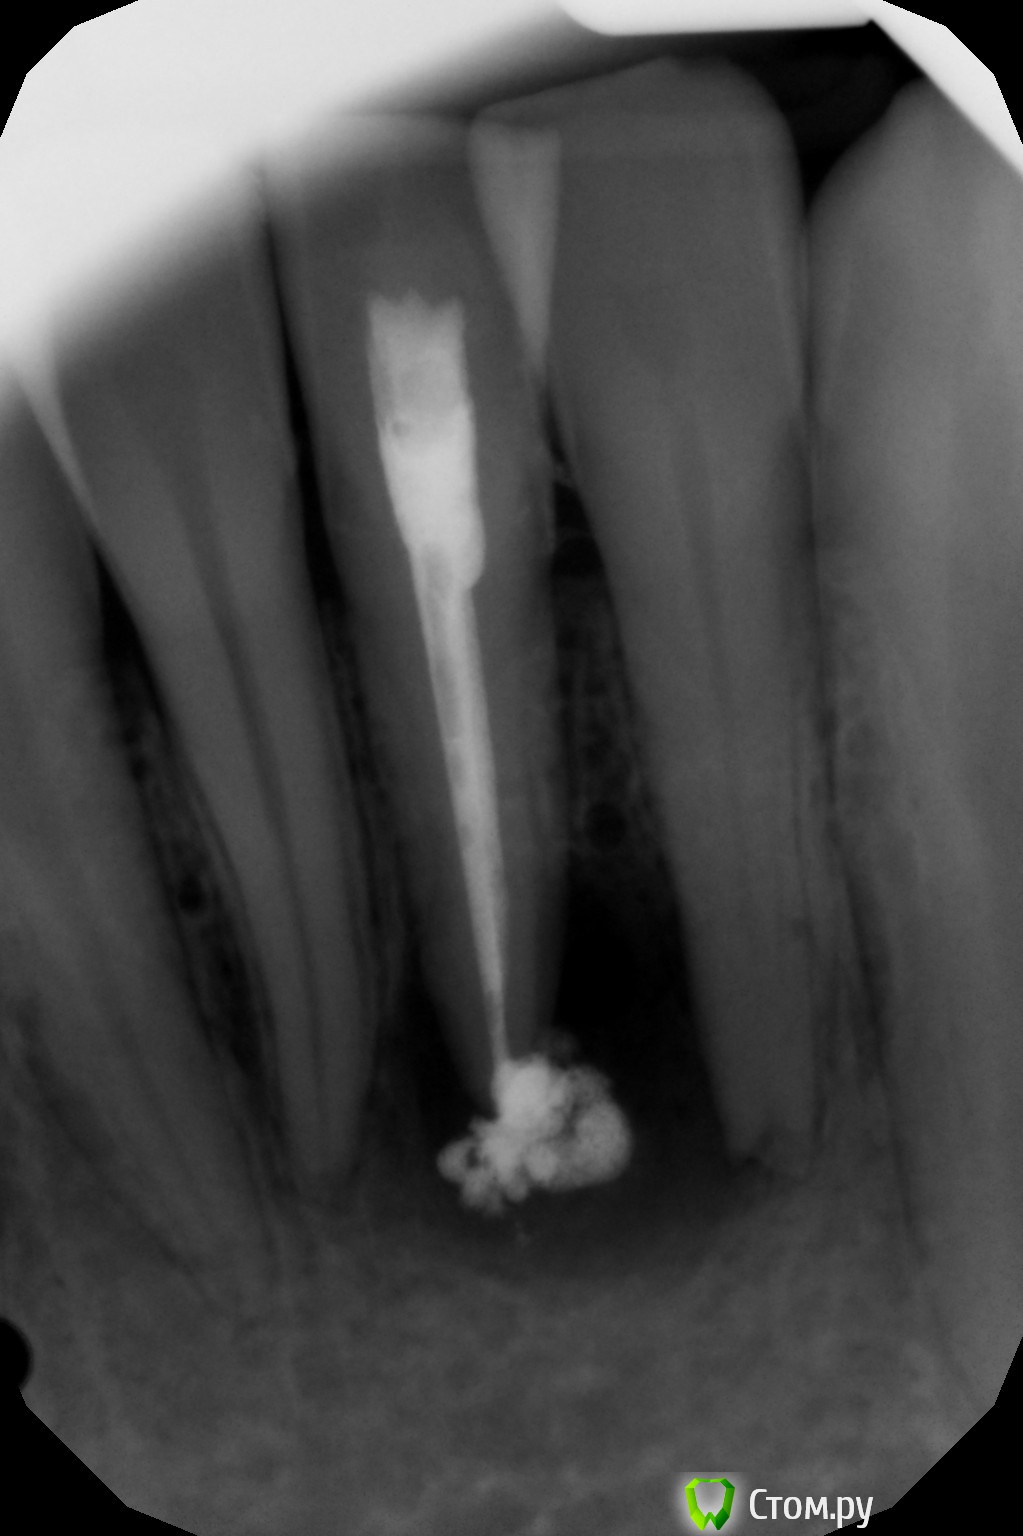

Григорий2014 Опубликовано 22 апреля, 2014 Поделиться Опубликовано 22 апреля, 2014 (изменено) Добрый день. Прошу вашего совета в дальнейших действиях и лечении.Ранее была травма нижних зубов 11 оба шатались. После фиксации проходил 2 недели с шиной и забыл об этом как страшный сон. Это было вроде 2008 году.Посещение 02.04.2014 диагноз радикулярная киста Г1 (сделали снимок почему-то он не сохранился прикрепить не могу). Канал почистили, заложили витапекс.Посещение 14.04.2014 промыли канал заложили витапекс повторно. Сделали снимок (во вложении).Следующее посещение назначили через месяц, сказали будут лечить гидрооксидом калия.Прошу дать заключение о успешности терапевтического лечения в данной ситуации. Заранее спасибо. Изменено 22 апреля, 2014 пользователем Григорий2014 Ссылка на комментарий

DmitrySH Опубликовано 22 апреля, 2014 Поделиться Опубликовано 22 апреля, 2014 Прошу дать заключение о успешности терапевтического лечения в данной ситуации. Заранее спасибо. Заключение о успешности лечение можно получить имея исходный снимок до лечения и снимок месяцев через 6 после лечения. Сейчас просто один из этапов. Нужно проверить жизнеспособность соседнего зуба, на снимке справа. Возможно он тоже вовлечен в процесс. 2 Ссылка на комментарий

DmitrySH Опубликовано 25 апреля, 2014 Поделиться Опубликовано 25 апреля, 2014 Спасибо а то уж поленился писать в очередной раз. Да, по снимку, очень похоже в этих зубах по 2 канала. Главное не пропустить при лечении. иначе ничего хорошего не выйдет. Ссылка на комментарий